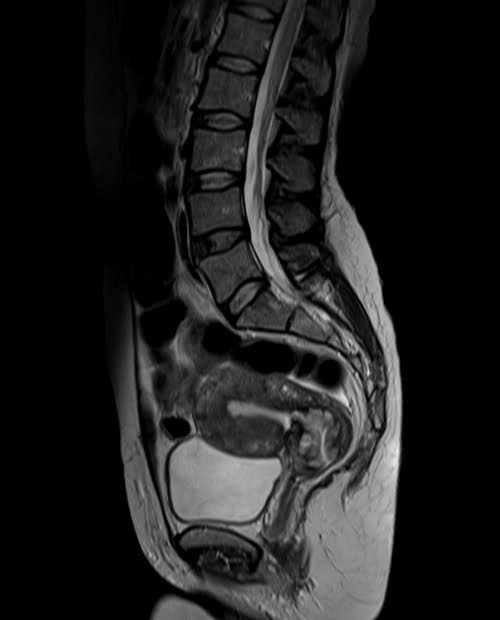

mri lumbosacral plexus sagittal t2 image 3 - MRI